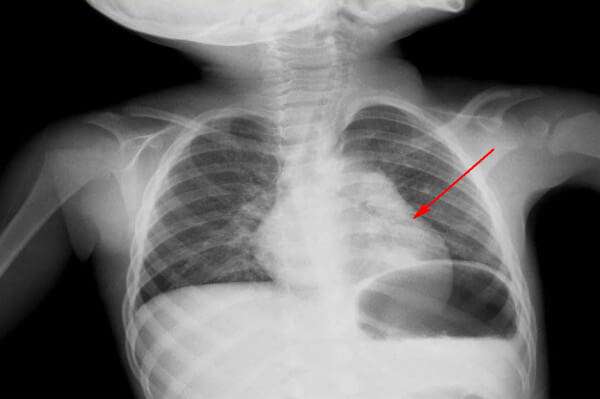

Острая пневмония имеет инфекционный характер развития. При заражении в легких начинается острый воспалительный процесс, сопровождающийся синдромом интоксикации и респираторной недостаточностью (дыхательная недостаточность). У пораженного ребенка появляются местные хрипы и укорачивается звук перкуссии. Альвеолы заполнены экссудатом (жидкостью).

По морфологическим формам медики выделяют еще одну классификацию. Это очаговая, сегментарная, церебральная и интерстициальная пневмония. Эти типы различаются степенью поражения и поражения сегментов легочной ткани.

Симптомы острой пневмонии учащаются через 4-6 дней после начала ОРЗ. В общий список симптомов входит быстрое повышение температуры (выше 38), интоксикация, сонливость и нарушение сна. Младенцы часто испытывают срыгивание и рвоту. В список респираторных симптомов входят кашель, одышка, вовлечение в дыхание дополнительных мышц (ребенок при вдохе сильно тянет межреберные мышцы).